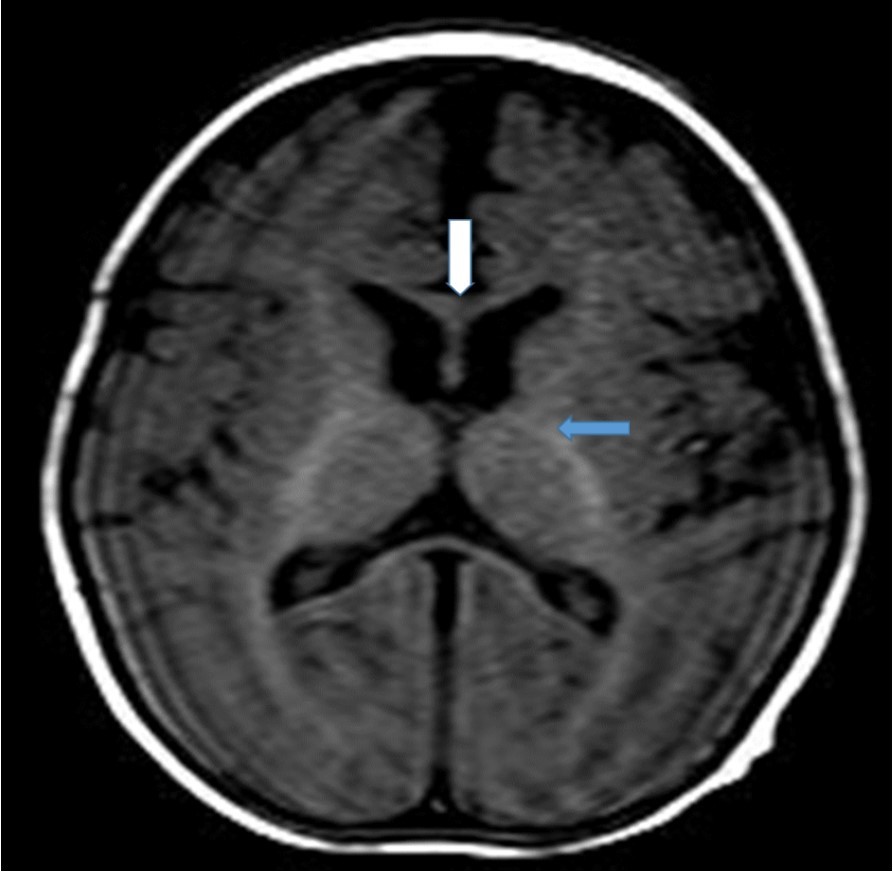

Cranial magnetic resonance imaging (MRI) was requested owing to the patient’s convulsion history and retarded development. The cranial MRI showed diffuse hypoplasia of the corpus callosum in the midline sagittal T2-weighted image (Figure 1 white arrow). T1-weighted imaging showed hypointensity due to delayed myelination of the genu of the corpus callosum (Figure 2, white arrow), which should normally appear hyperintense like the posterior limb of the internal capsule (Figure 2, blue arrow).

Figure 2.T1-weighted magnetic resonance image of the patient (7-month-old girl). The genu of the corpus callosum is hypointense due to myelination delay. In this age group, the genu of the corpus callosum should become hyperintense similar to the posterior limb of the internal capsule (blue arrow) due to myelination.